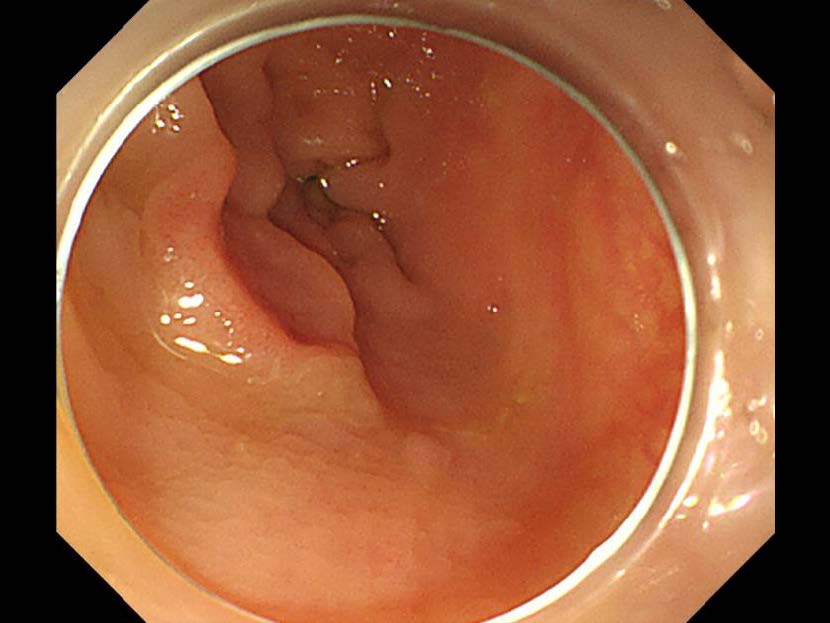

消化管Mapping~大腸~ 2021.10.27

消化管Mapping

消化管Mapping~大腸~

消化器内科

内視鏡検査・治療